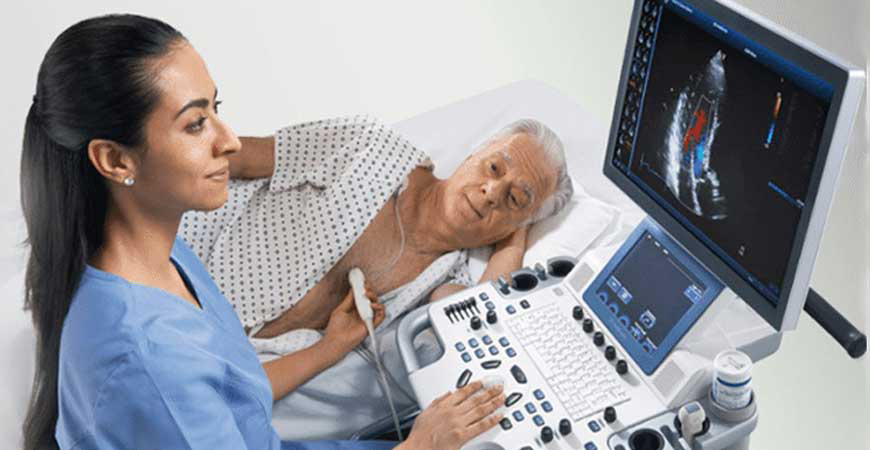

2D ECHO